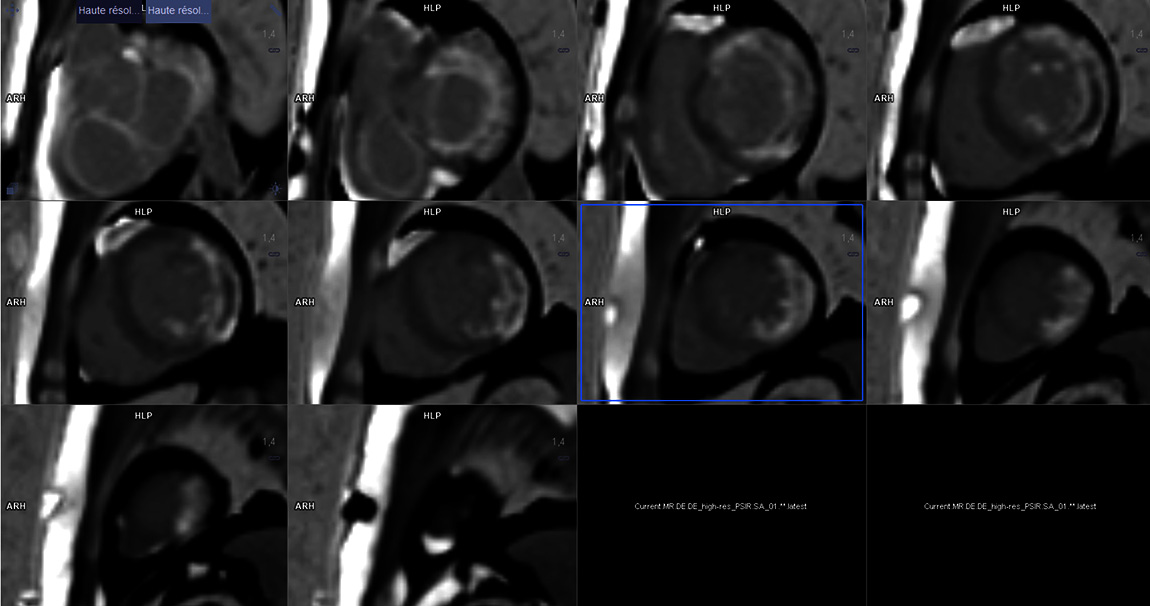

En raison d'une altération de la FEVG constatée dans les suites en ETT, une IRM myocardique objective une FEVG à 38 % et la présence d'une séquelle de nécrose transmurale sur 7 à 8 segments du territoire latéral débordant en antérieur et inférieur.

Une IRM myocardique de contrôle a été réalisée à 3 mois et objective une amélioration de la FEVG à 47 % malgré les séquelles transmurales persistantes.